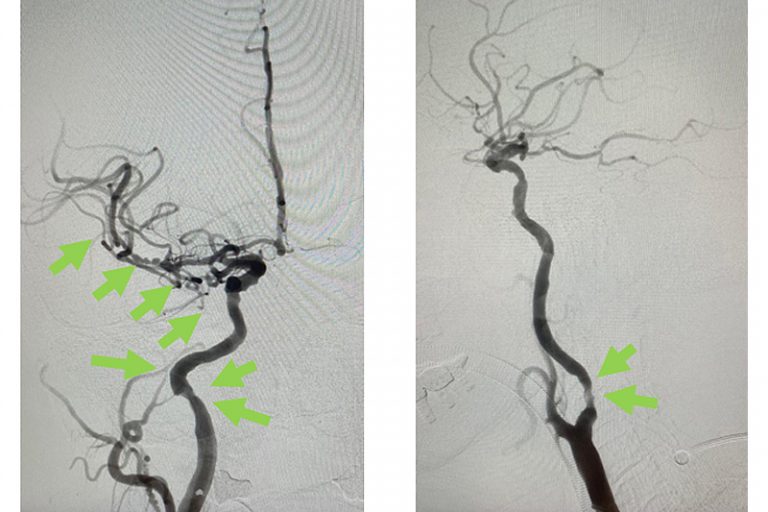

圖:導管遊走到病人右邊的頸和腦部血管大動脈,進行機械式血栓吸取

羅先生被送往私家醫院的第一步是進行緊急磁力共振造影,報告顯示羅先生右邊頸和腦部血管大動脈全部都被血栓堵塞着,右邊大腦缺血水腫,導致左邊手腳冇力和神智半昏迷。經過腦血管外科醫生的診斷和急救,在全身麻醉下,醫生使用尤如髪絲微細的導管,經過病人右邊大腿的腹股溝的大動脈而入,導管再經過腹部和胸腔的大動脈一直向上,遊走到病人右邊的頸和腦部血管大動脈,進行機械式血栓吸取內血管治療急救。

圖:血栓被吸取後, 右頸和腦血管都給順利打通,腦部缺血情況立即得到改善。

經過1小時的血管急救,所有血栓都被移除,羅先生的右頸和腦部血管都給順利打通,腦部缺血情況立即得到改善。血栓被吸取後,腦血管外科醫生發現羅先生的右頸內動脈有嚴重血管狹窄的情況,這個狹窄就是羅先生中風的主要原因。醫生因此植入血管支架來重新擴張狹窄的血管,以防止羅先生將來中風復發。全身麻醉清醒後,羅先生的大腦意識和手腳活動能力即時好轉,他其後再被送回另一間公立醫院繼續康復治療。

圖:血栓被吸取後,發現右頸內動脈血管嚴重狹窄是中風的主要原因。

圖:醫生植入血管支架來重新擴張狹窄的血管,以防止將來中風復發。